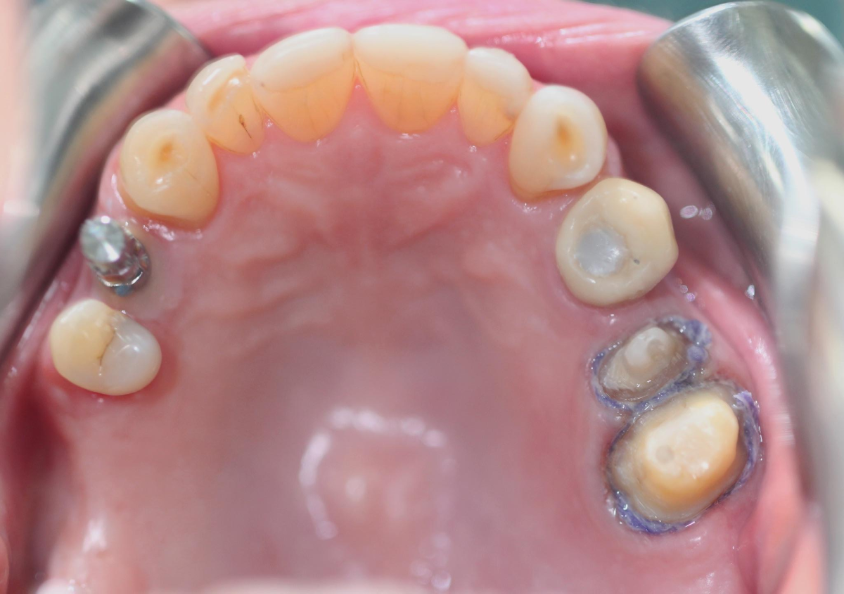

歯を準備する (25と26)。 コンポーネント (伝達印象) は、インプラント (歯14) 上に保持される。

引き込みコードによる歯肉変位後の歯肉溝内の材料の流動性に注意してください。これにより、歯の周囲全体の優れたレプリカが実現します。